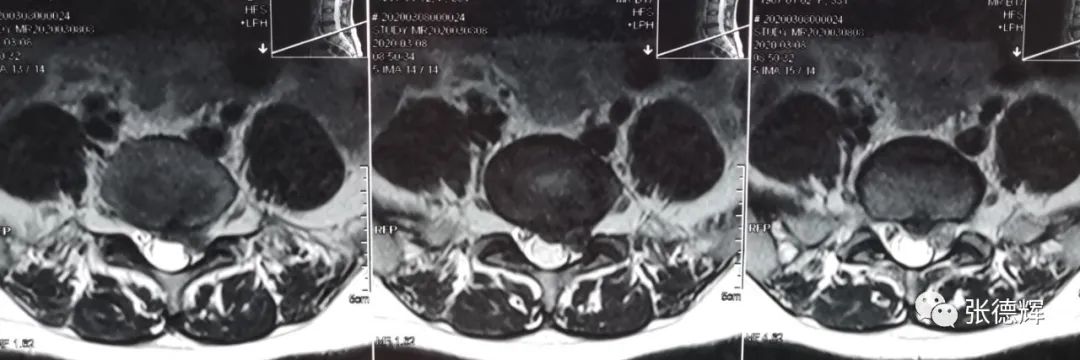

影像检查提示:腰5-骶1椎间盘左后突出,神经根受压(腋下型突出)

腰椎核磁共振检查,矢状位片提示腰5-骶1椎间盘突出,横断位片可见突出物位于神经根腋下